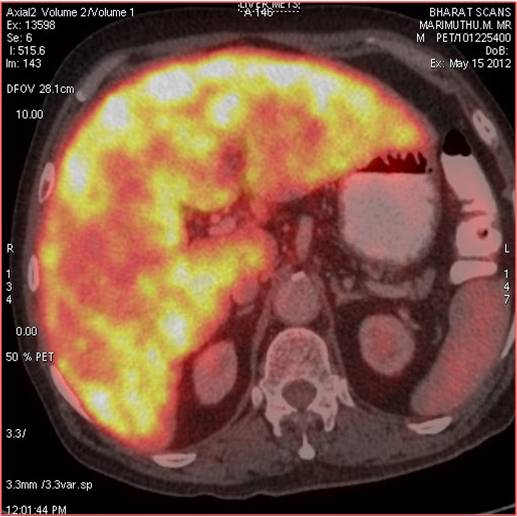

CT scan of the abdomen confirmed the findings ; For further clarification PET whole body scan was done at a centre in Chennai. The following images are from that.

Extensive FDG avid hepatic metastases involving both lobes.